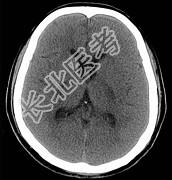

- 单项选择题男,57岁, 头痛、头晕1周,言语不清, 饮水呛咳两天,既往有鼻咽癌病史, 给予放射治疗,CT检查如图所示, 最可能的诊断是 ( )

A、放射性脑病

B、脑梗死

C、脱髓鞘病变

D、胶质瘤

E、脑炎